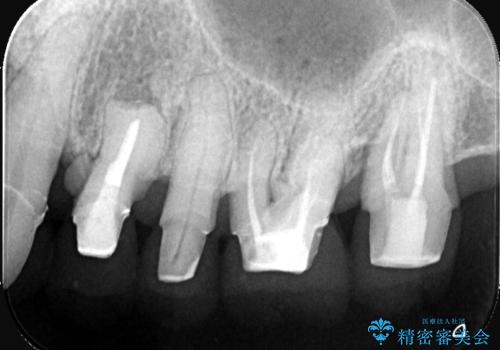

難症例の奥歯も3ヶ月で機能回復!抜歯即時インプラントでスピード解決